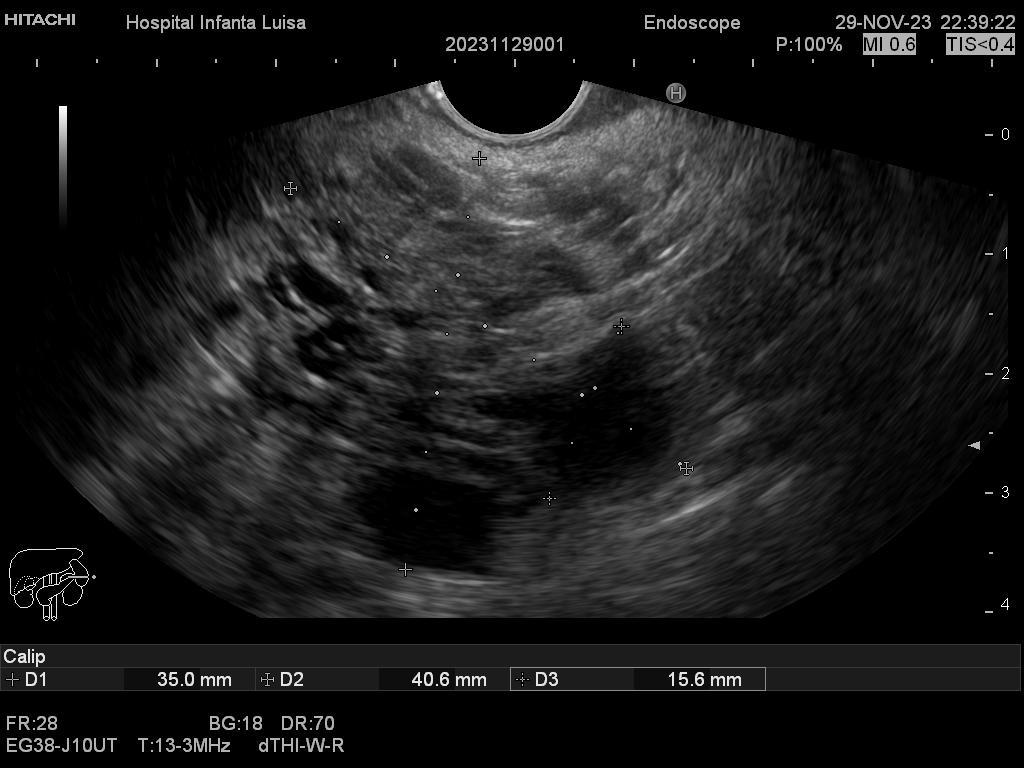

Mediante dicha exploración se explora minuciosamente los tramos mencionados, permitiendo valorar distintas patologías como lesiones propias de la pared de estos órganos (determinado su profundidad y extensión), o lesiones que quedan en órganos anexos, pero por fuera, de ahí la importancia de la visualización ecográfica, como páncreas, mediastino, hígado, diferentes adenopatías o masas indeterminadas previamente, entre otros.

Igualmente, es una técnica básica hoy día en el estudio de todo tipo de lesiones pancreáticas, en la determinación de formaciones subepiteliales esofágicas, gástricas (más frecuentes) o duodenales, o en el estadiaje de patología tumoral a estos niveles. La Ecoendoscopia permite la toma de biopsias a estos niveles, con control endoscópico y ecográfico, siendo una técnica de gran rentabilidad diagnóstica y seguridad.